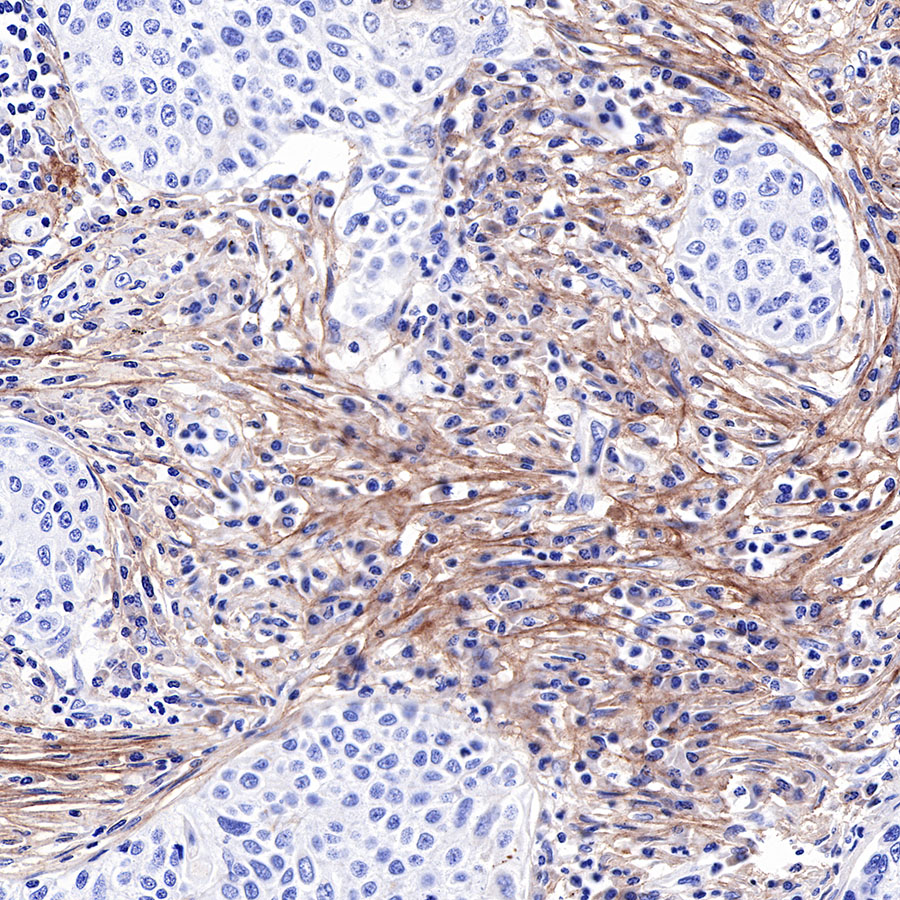

IHC shows positive staining in paraffin-embedded human lung squamous cell carcinoma. Anti-COL3A1(PIIINP) antibody was used at 1/500 dilution, followed by a HRP Polymer for Mouse & Rabbit IgG (ready to use). Counterstained with hematoxylin. Heat mediated antigen retrieval with Tris/EDTA buffer pH9.0 was performed before commencing with IHC staining protocol.